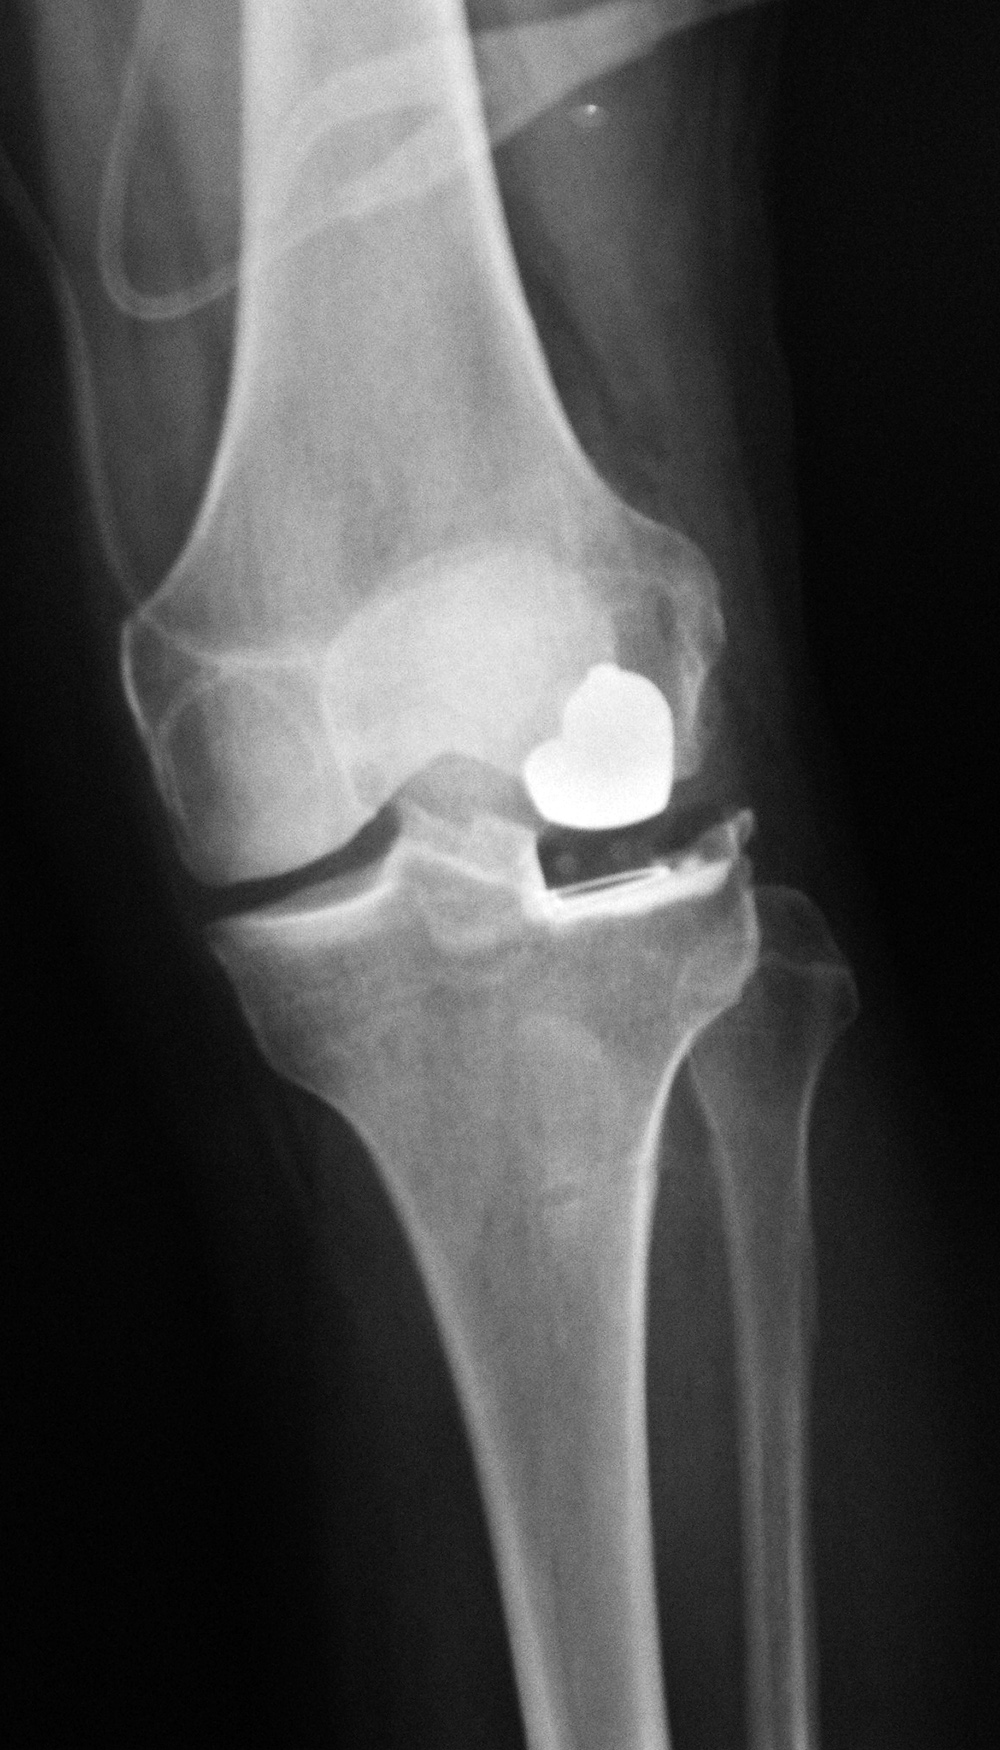

| Biomet XPA Bicruciate Preserving total knee arthroplasty |

| 67 year-old woman. A surgical drain is present from recent surgery. From Taljanovic, 2005 |